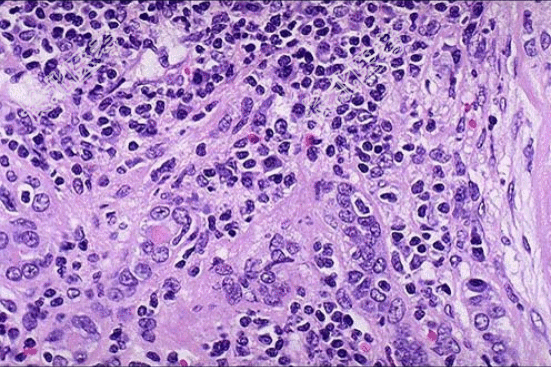

- [材料题] 患者女性,53岁,双肾缩小,表面可见不规则瘢痕,两侧改变不对称,切开,皮髓质界限不清,肾乳头萎缩,肾盏和肾盂因瘢痕收缩而变形,肾盂黏膜粗糙;巨检如图,镜下如图所示。